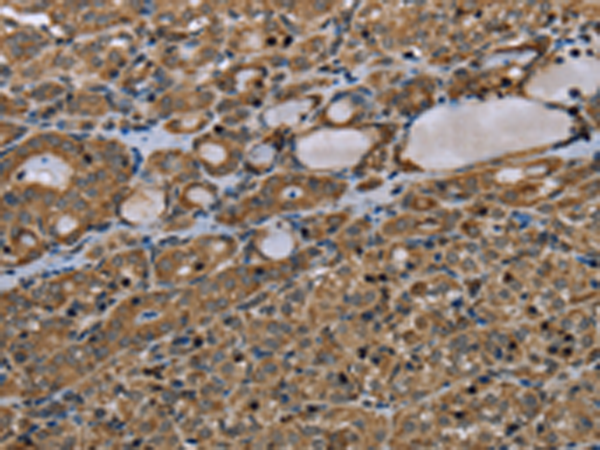

分类: 科研抗体货号: P05121别名:应用: WB,IHC反应种属: Human